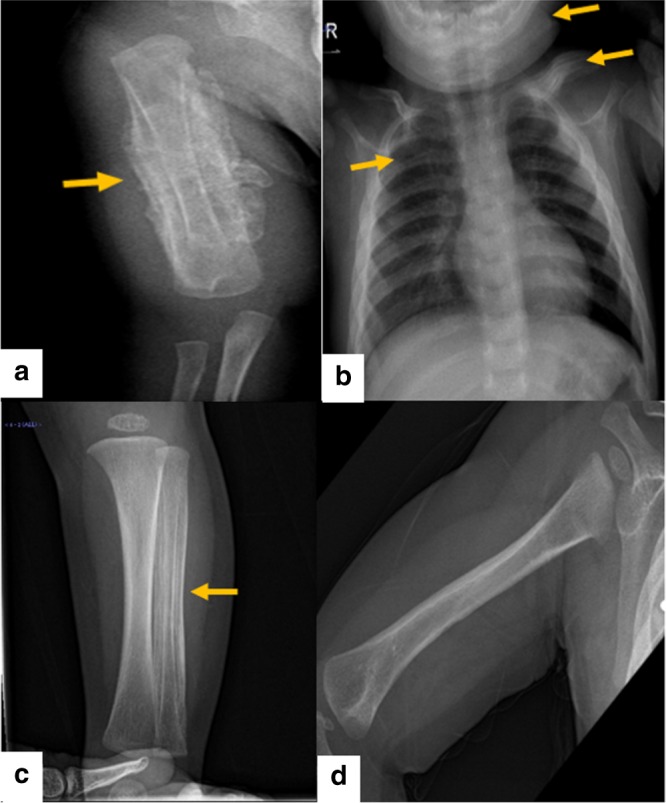

對右臂進行 X 光檢查,顯示沿右肱骨的整個骨干骨膜反應(yīng)旺盛(圖 1a)。 進一步評估包括 X 線骨骼檢查,顯示一側(cè)肩胛骨、一根腓骨、下頜骨和許多肋骨有明顯的骨膜反應(yīng)(圖 1b)。 根據(jù)臨床和放射學(xué)檢查結(jié)果,診斷為 ICH。 盡管德托尼-卡菲病可能具有短暫性,但開始使用吲哚美辛(每天 5mg/kg)治療,并且病變在幾個月內(nèi)有效消失,正如后續(xù)放射學(xué)檢查所證明的那樣(圖 1c)。 經(jīng)過 1 年的隨訪,患者有效康復(fù),沒有骨骼畸形和/或升高的炎癥標志物。 他仍在服用低劑量的消炎痛(每天 1mg/kg)。

患者的射線照相檢查。 a 沿右肱骨整個軸的骨膜反應(yīng)。 b 沿左鎖骨、肋骨和下頜骨的骨膜反應(yīng)。 c 沿腓骨的骨膜反應(yīng)。 d 肱骨骨膜有效消退